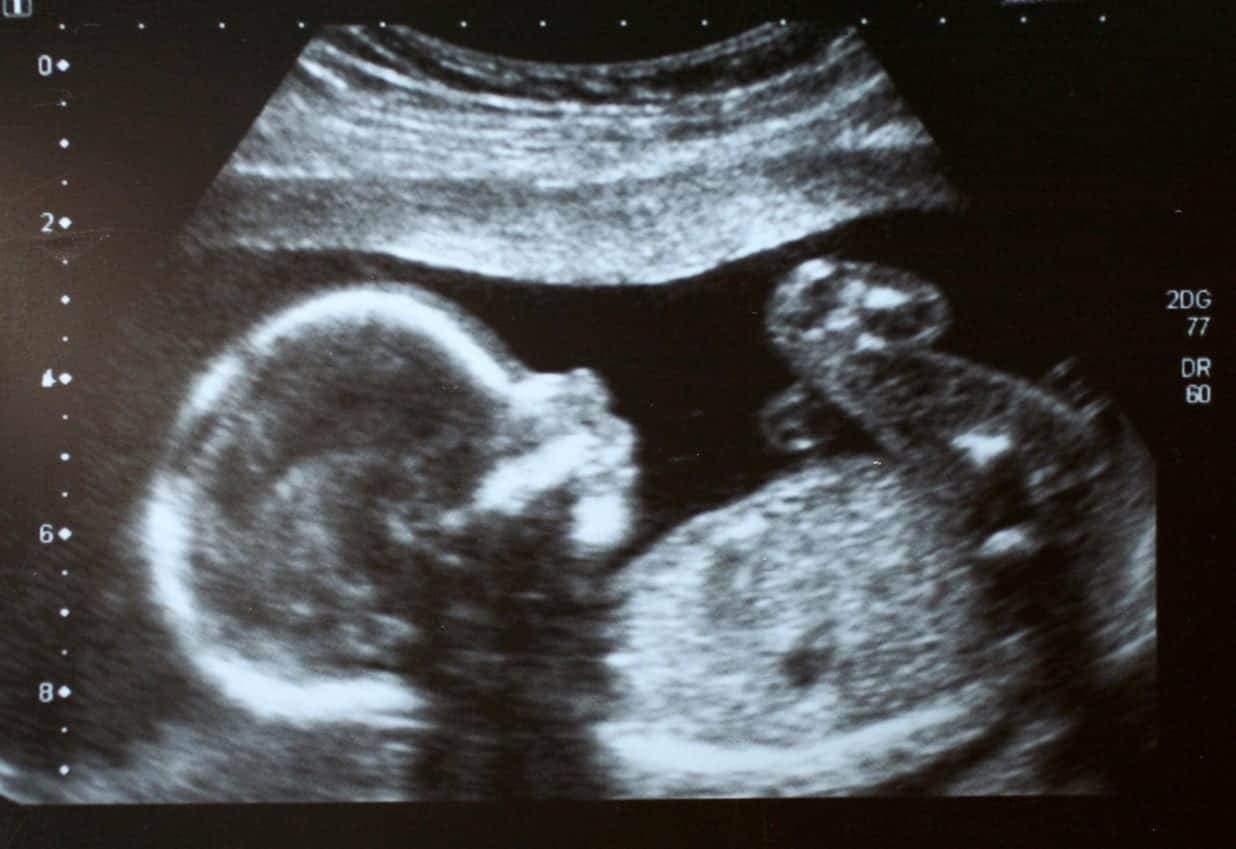

When women become pregnant, they must make many difficult decisions. One decision that is often guided by medical providers is whether they should continue to take their prescription drug. For women with epilepsy or migraines, Depakote is a popular anticonvulsant medication. However, studies have shown that Depakote is linked to birth defects. Sadly, many doctors and patients were not given enough information by Depakote’s manufacturer, Abbott Laboratories, regarding the risk of birth defects. If women who could get pregnant had all the information, they may have chosen a different medication.

The New England Journal of Medicine released a study in 2010 that was conducted by European researchers. This study showed an increase risk of birth defects in babies whose mothers took Depakote during the first three months of their pregnancy. Additionally, this study also revealed that pregnant women who take Depakote have 12 times the risk of having a baby with spina bifida than women who did not take Depakote during their pregnancy. Spina bifida is one of the most common neural tube defects.

If you took Depakote during your pregnancy and your child was born with a birth defect or suffers from lower cognitive function, you may be eligible to receive compensation. Depakote lawsuits are being filed by mothers to get the compensation they deserve and to help them care for the lifelong affects Depakote had on their child.